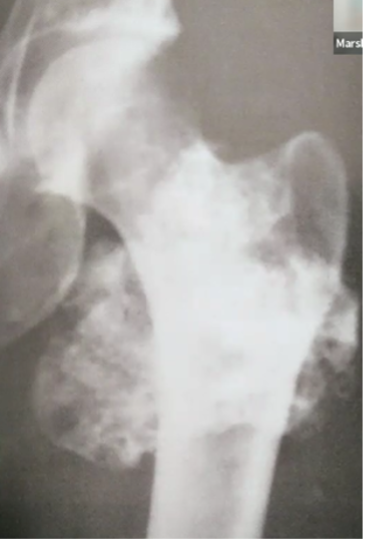

ostéosarcome

malin 2e plus fréquent, très agressif

o Réaction périostée : spiculée = sunburst apparence

o Sclérotique/lytique ou mixte

o Expansion dans les tissus mous : cumulus cloud

o Triangle de Coddman : signe que le cortex est brisé

o NE TRAVERSE PAS LA PLAQUE DE CROISSANCE NON OSSIFIÉE ou l’articulation : car distribution hématologique VS infection ne respecte PAS la plaque de croissance